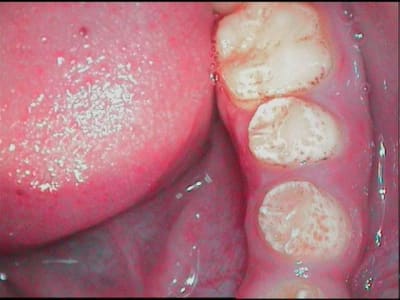

jeune patiente 11ans, je l'ai suivie il y a quelques années, pour les lacteales et sans probleme.

je la revois aujourd'hui, 11ans, et la denture definitive ne dit rien de bon pour son avenir....

je connais la famille, il n'y a aucun antécédent (connu), le controle de plaque est tres bon (elle a gardé en memoire les conseil d'hygiène, tant mieux et heureusement!!!), sa santé generale est tres bonne, ses habitudes alimentaires ne me laisse rien craindre...

pour les anterieures j'aimerais eviter les facettes, et m'orienter vers des prepa pelliculaires, pour les post je peux sceller les puits et fissures aux verres ionomeres, mais pour le "piqueté" général d'email, en buccal interprox, etc...

Si je me souviens bien, nous avions fait des "chips" céram de canine à canine (ce n'est pas moi qui les ai réalisées donc je ne peux pas t'aider sur ce point)et en postérieur des scellements de sillons + puits avec surveillance ultra régulière des points de contacts (défectueux en général)

Notre patiente n'avait pas une bonne hygiène contrairement à la tienne donc nous avions appliqué un vernis à la chlorhexidine partout.